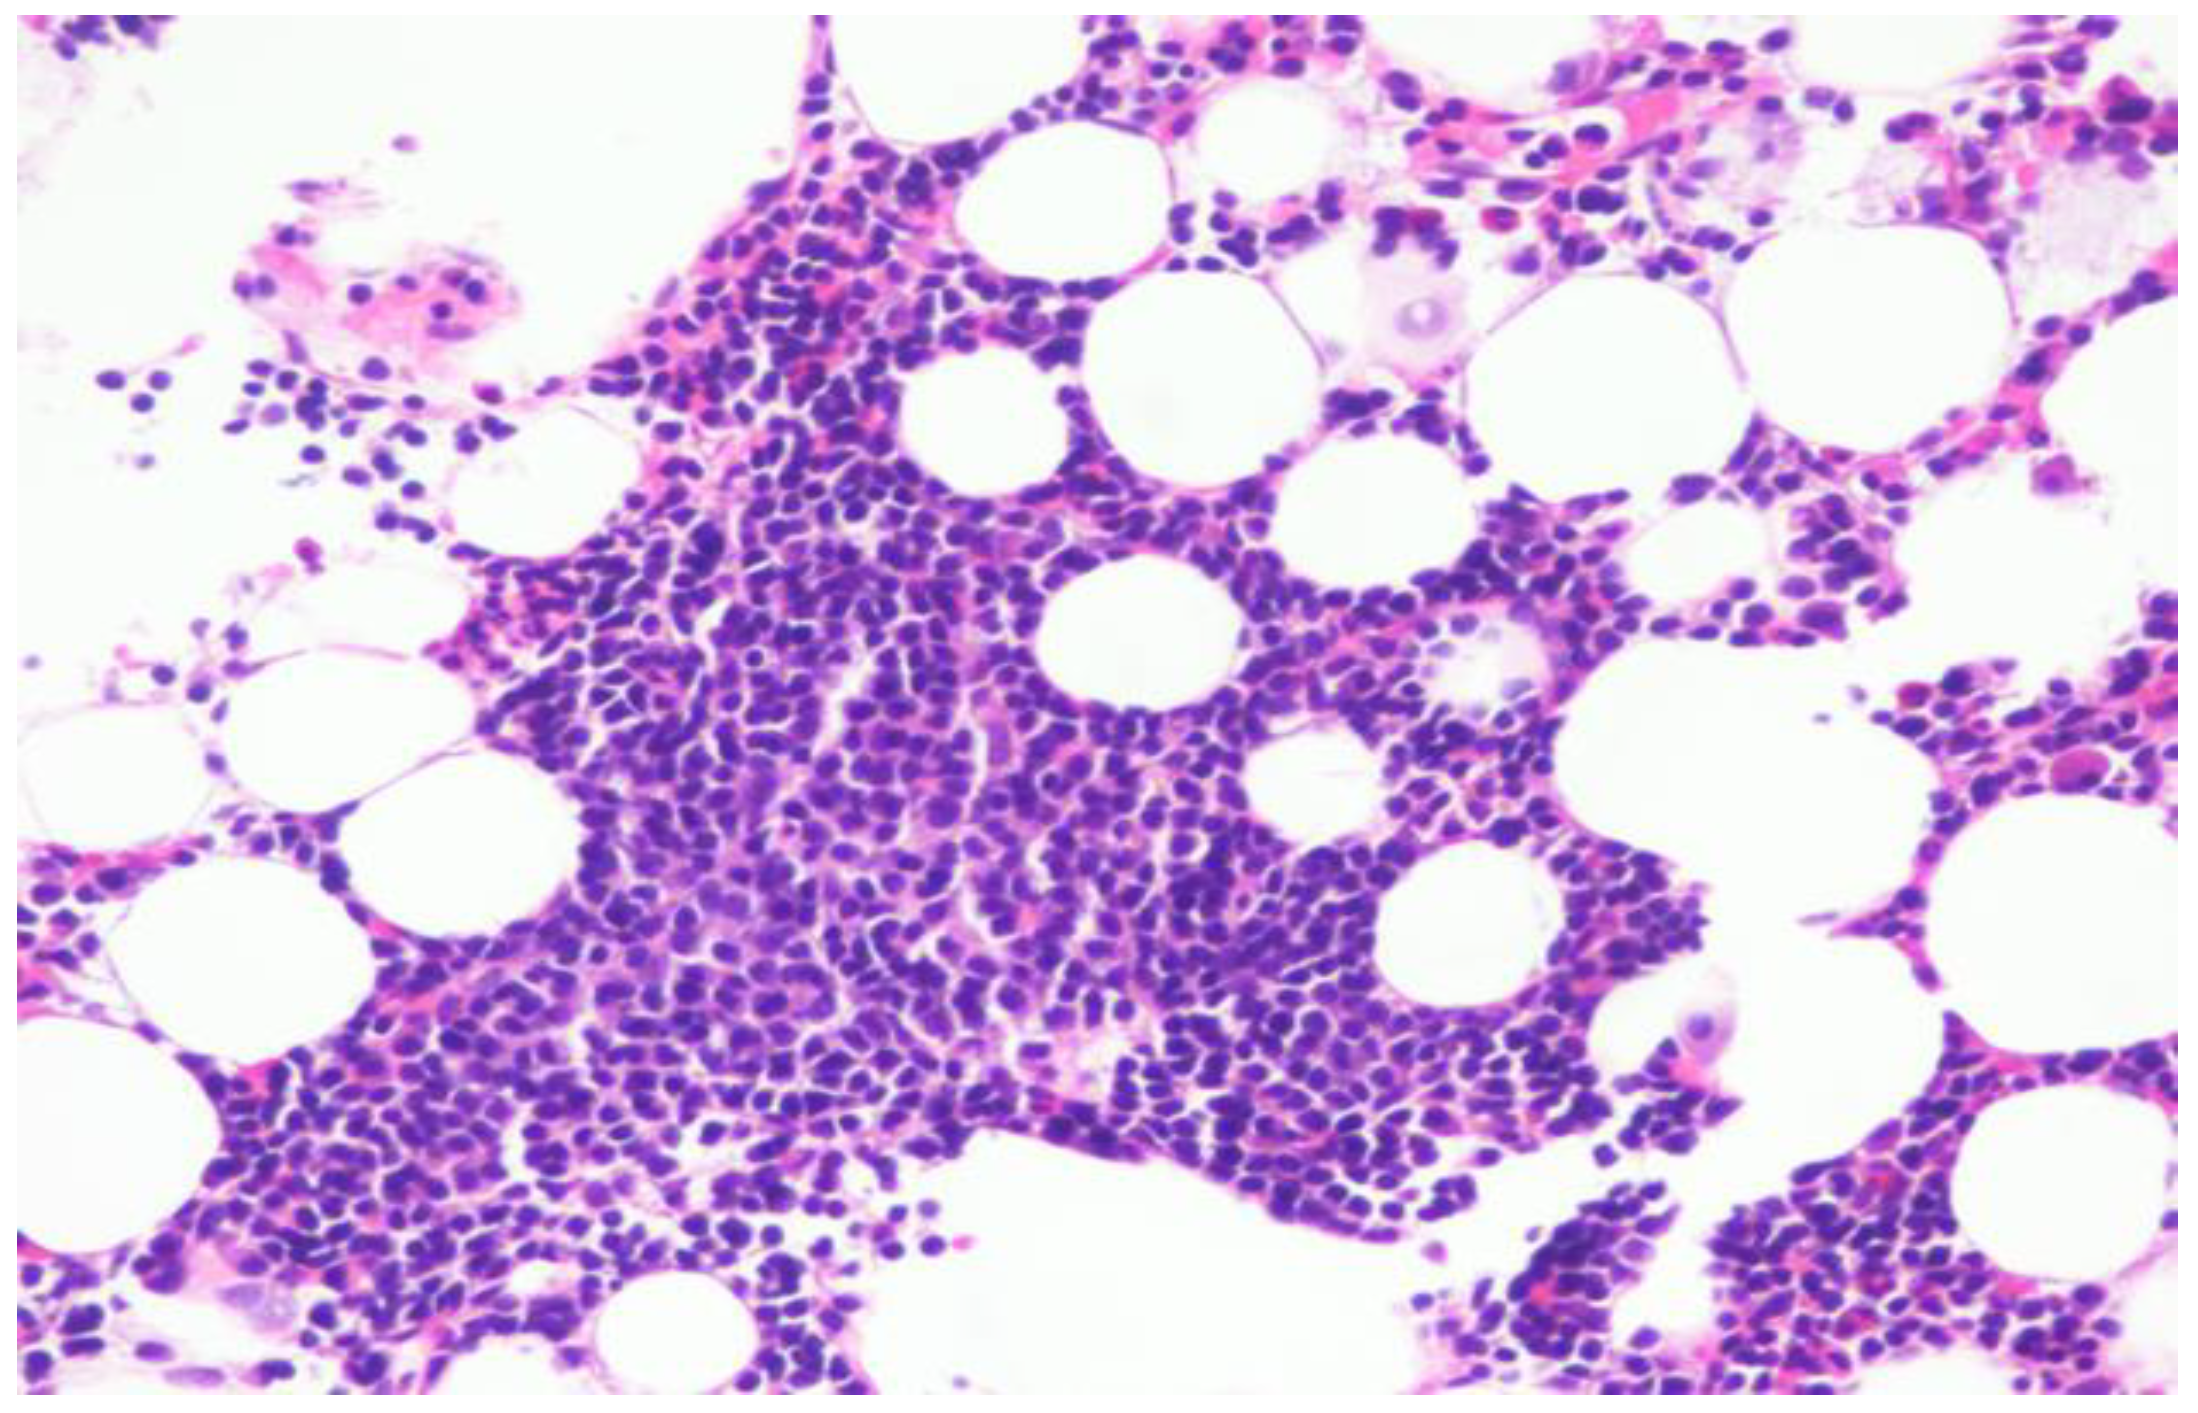

Repeat bone marrow biopsy showed hypercellular marrow with persistent/recurrent involvement by CLL with 35% lymphocytes (Figure 2 and Figure 3). Flow cytometry analysis on bone marrow showed the presence of aberrant clonal B cells (~14% of total events) with the following immunophenotype positive for CD5, CD19, CD20 (dim), CD22, CD23 (subset), CD45, HLA-DR, CD11c (subset), surface Lambda light chain (dim) with a Kappa to Lambda ratio of <1:10 and negative for CD10, CD103, FMC-7, CD38, and surface Kappa light chain. Molecular studies on the bone marrow aspirate did not detect the deletion of 13q, ATM/11q, or TP53 mutation, but was positive for trisomy 12.

Figure 3. Hypercellular bone marrow with trilineage hematopoiesis as well as increased lymphocytes.